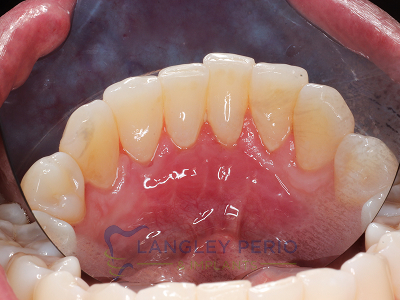

Case 2

Connective tissue grafting was done to cover exposed root surfaces to help to prevent root cavities from developing and reduce temperature sensitivity.